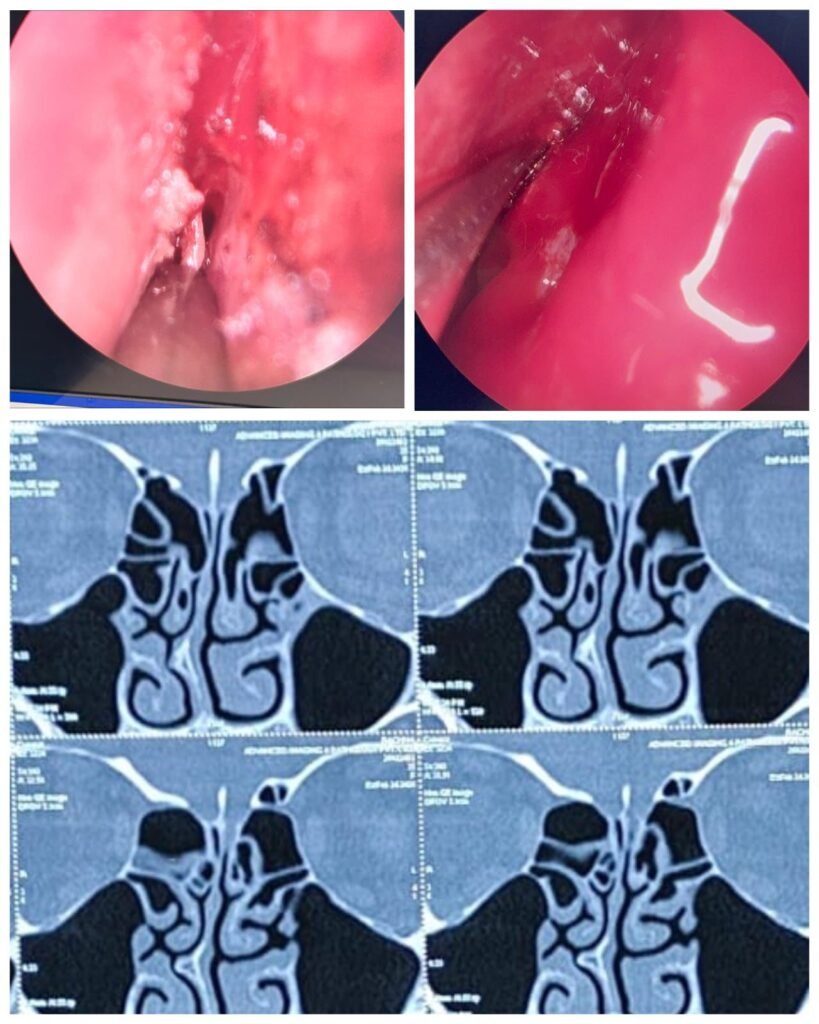

ENT surgeons at SNMC Agra performing minimally invasive CSF Rhinorrhea repair surgery on a 35-year-old female patient using endoscopic (telescope) method, ensuring precise and scar-free treatment.एसएनएमसी आगरा में दूरबीन विधि से सफल सीएसएफ राइनोरिया ऑपरेशन

ईएनटी ओपीडी में प्रारंभिक जांच और सीटी स्कैन के बाद पता चला कि मस्तिष्क और नाक की गुहा के बीच अस्थि दोष (Bone Defect) है, जिसके कारण मस्तिष्क का मेरु द्रव (CSF) रिसाव कर रहा था। इस तरह की स्थिति न केवल असुविधाजनक बल्कि गंभीर जटिलताओं का कारण भी बन सकती है।

बीते 13 मार्च, 2026 को प्रोफेसर डॉ. धर्मेंद्र कुमार और उनकी विशेषज्ञ टीम ने एंडोस्कोप (दूरबीन) विधि का उपयोग कर इस दोष का सफलतापूर्वक मरम्मत किया। इस तकनीक में किसी भी बाहरी चीरे या निशान की आवश्यकता नहीं होती, जिससे मरीज की रिकवरी तेज और सुरक्षित होती है। डॉ. धर्मेंद्र ने बताया कि यह एक अत्यंत संवेदनशील सर्जरी थी, जिसमें मस्तिष्क की झिल्ली और नाक के बीच मार्ग की सुरक्षा सर्वोपरि थी।